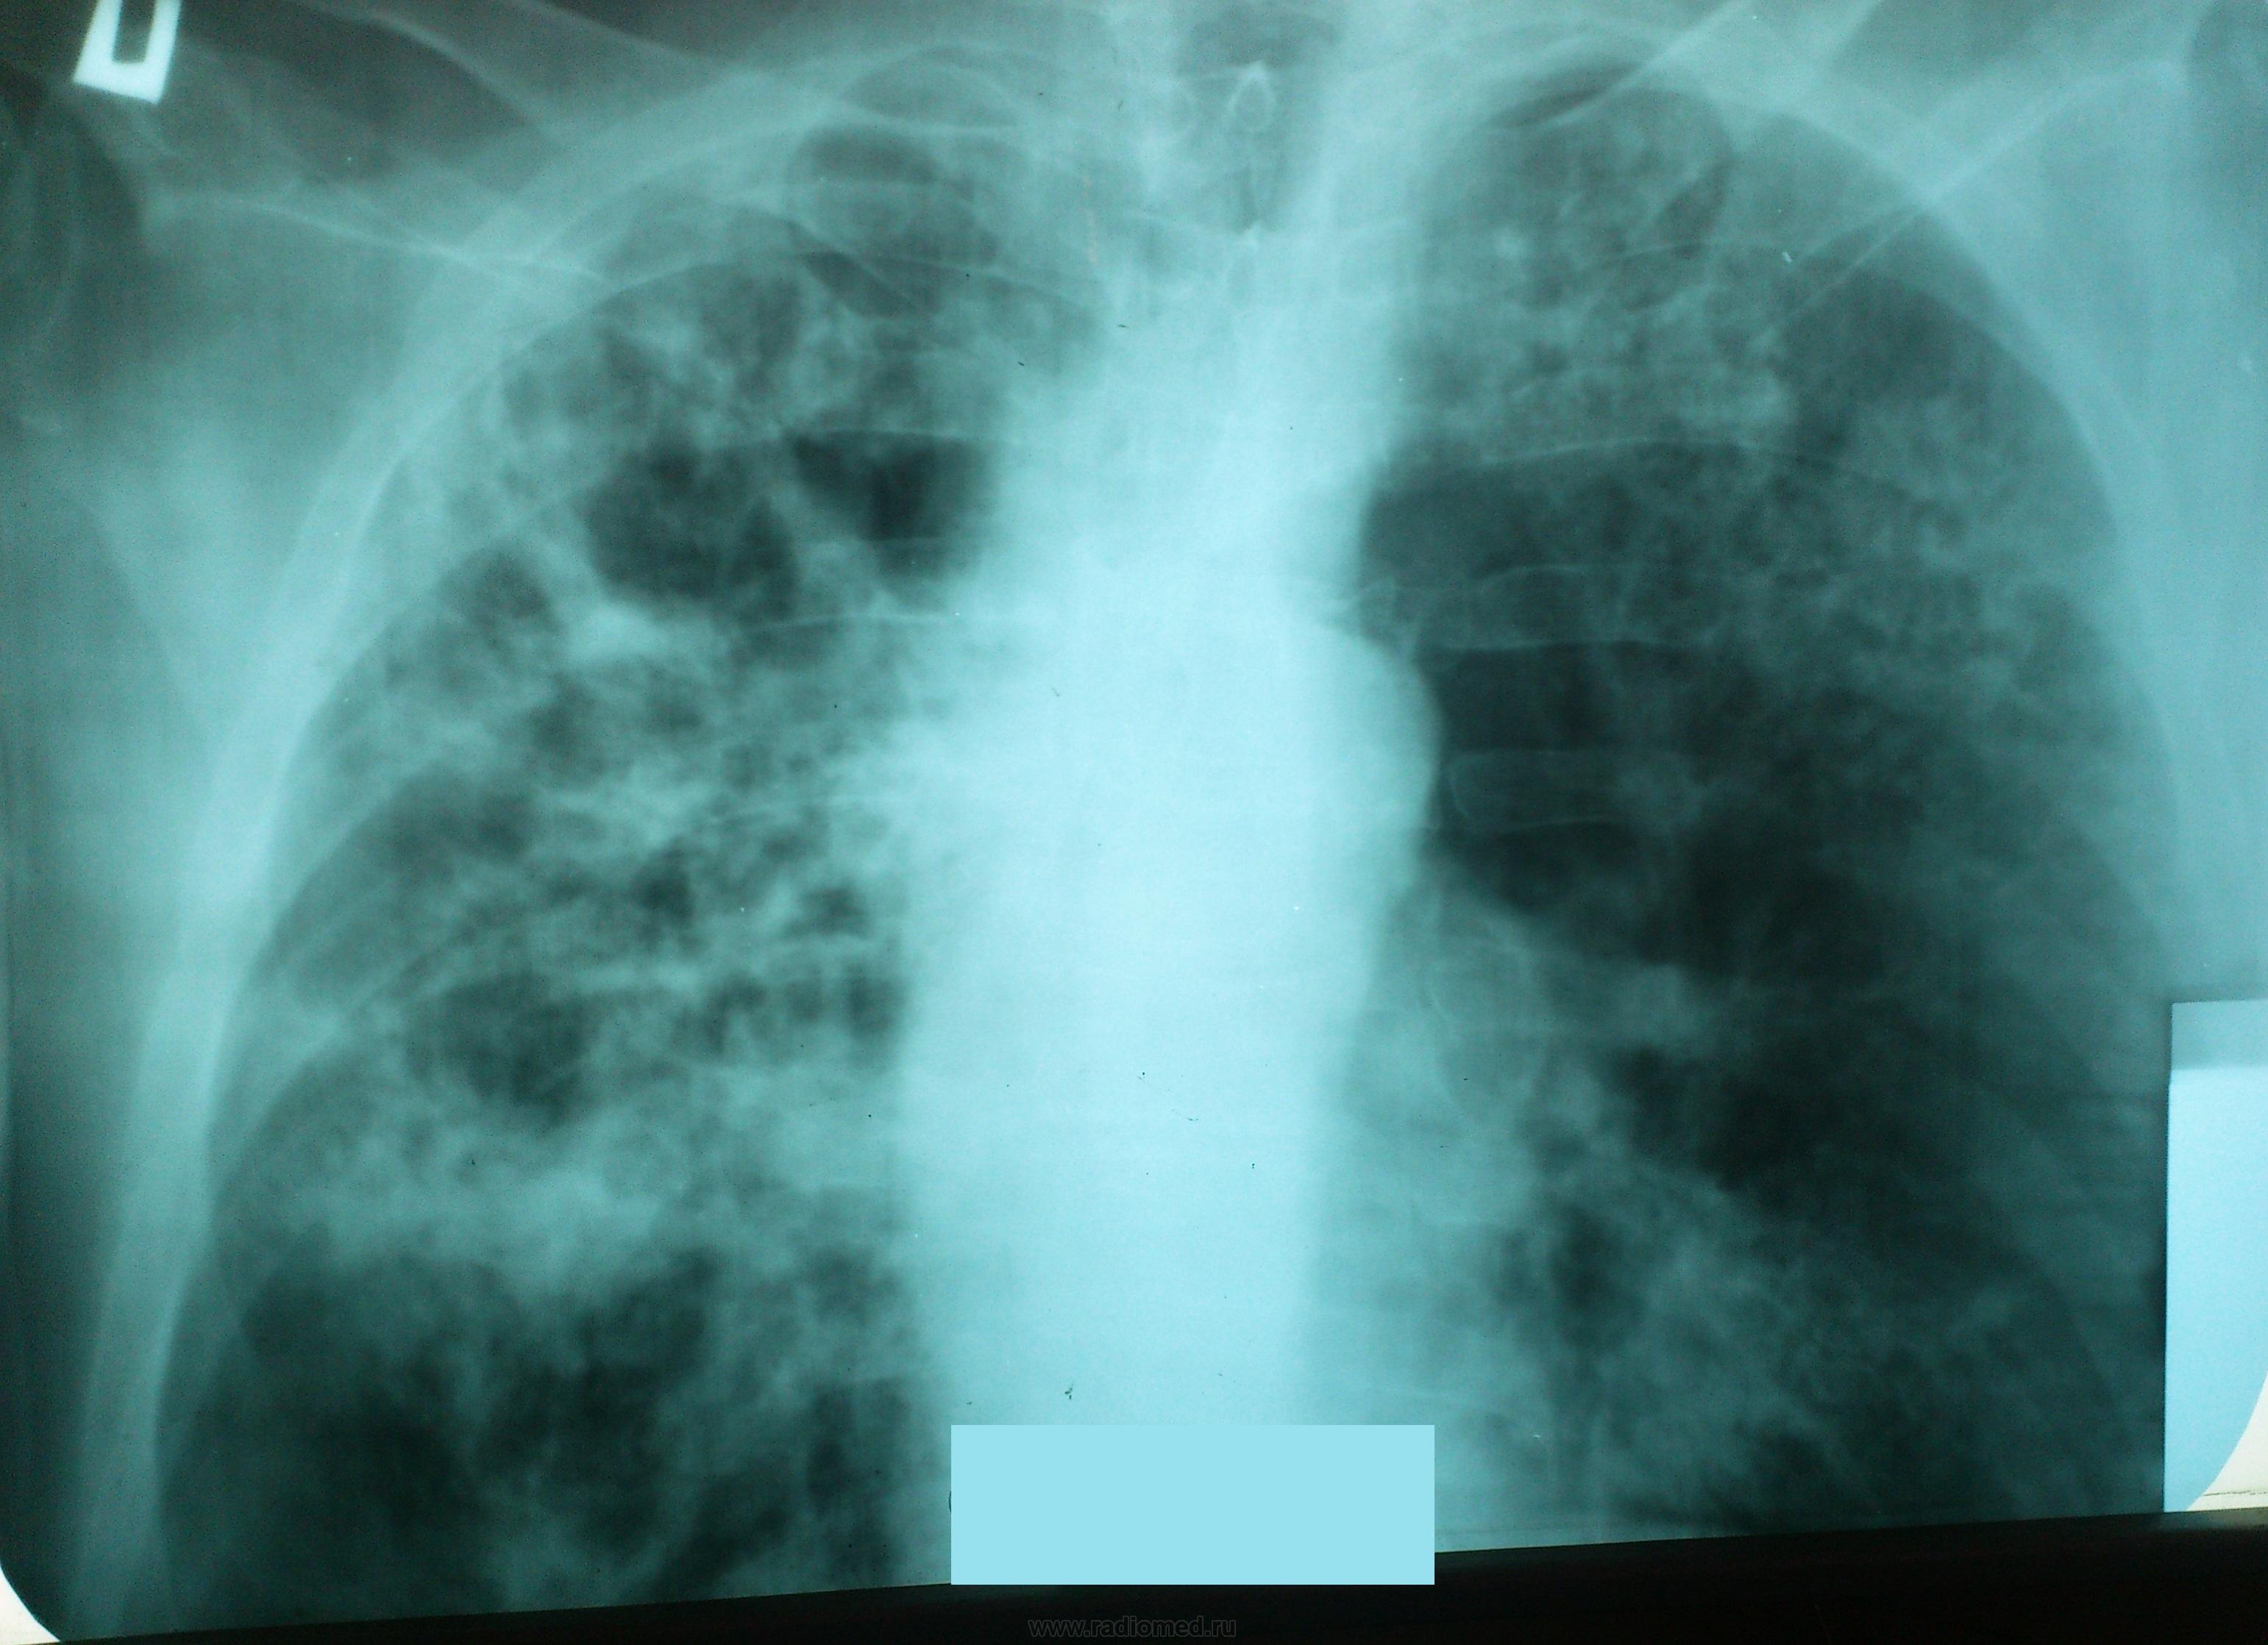

Снимок легких при туберкулезе является важным методом диагностики этого заболевания. На рентгеновских снимках можно увидеть изменения в легких, которые свойственны туберкулезу.

Диссеминированный туберкулез на рентгенограмме

Диссеминированный туберкулез рентген

Острый диссеминированный туберкулёз лёгких рентген

Диссеминированный туберкулёз лёгких рентген

Фотографии снимков легких при туберкулезе

В данной статье представлены многочисленные фотографии снимков легких при туберкулезе, чтобы помочь вам понять, как выглядят изменения легких на рентгеновских снимках при этом заболевании.